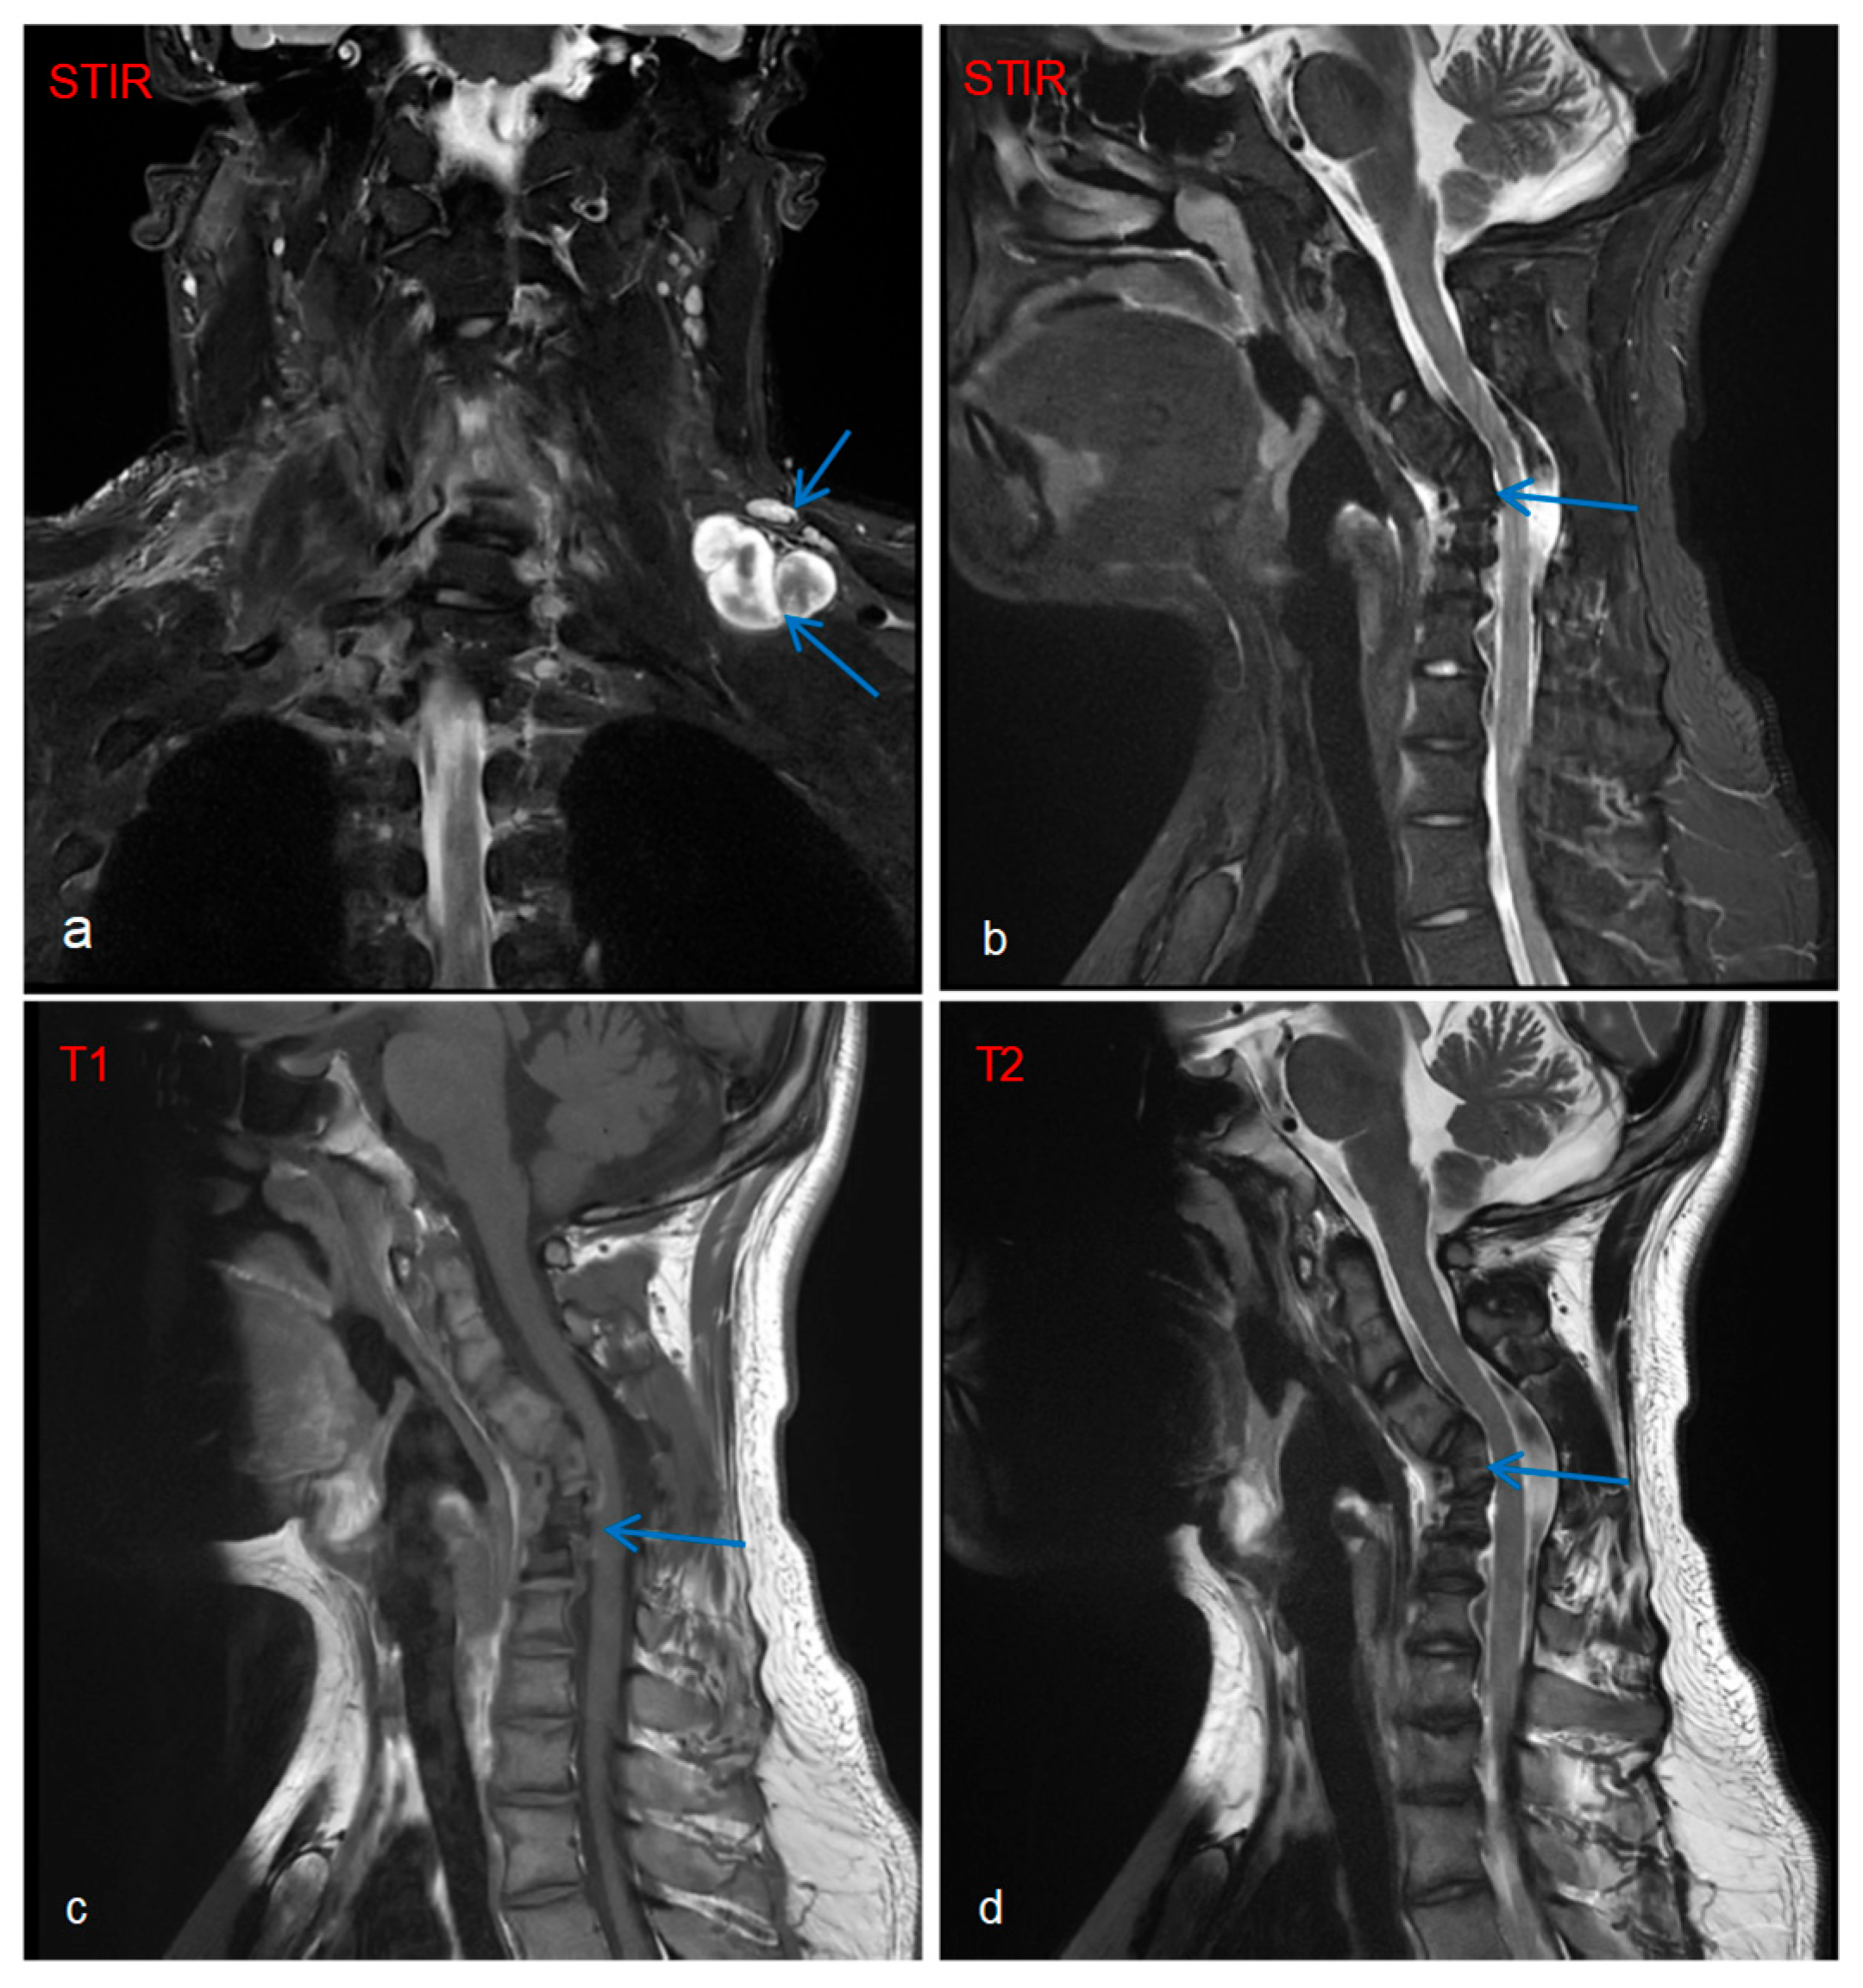

Imaging and ancillary investigation results were as follows: Whole-body PET-CT showed multiple metabolically active nodules/masses in the left posterior supraclavicular region, right deep axillary area, posterior to the right first rib, and mediastinal inferior retrocardiac region, suggestive of neurofibromas. Whole-body and targeted MRI revealed plexiform neurofibromas (Figure 2a), with concurrent findings of C4–C6 vertebral body deformities and cervical kyphosis (Figure 2b–d).

Compared to rare factors such as cardiogenic embolism and inherited fibrinolytic inhibition that cause cerebral infarction in NF1 patients, plexiform neurofibroma (PNF) represents the most characteristic and severe complication of NF1, with an incidence of 30%~60%. Although PNF is a benign tumor, it can lead to severe consequences including disfiguring lesions, persistent pain, and may even form a fatal compression on the spinal cord [17]. Case reports have documented the locally aggressive behavior of PNF and its significant association with cervical deformities [18]. In this case, the patient presented with a left brachial plexus plexiform neurofibroma, accompanied by morphological distortion of the C4-C6 vertebral bodies and cervical kyphosis. Therefore, the patient’s cervical structural abnormalities are most likely attributed to the invasive effects of the left brachial plexus plexiform neurofibroma, supported by the correlation between plexiform neurofibroma localization and vertebral deformity observed on imaging.

Figure 2. Cervical spine MRI: Target sign observed on fat-suppressed STIR sequence, characterized by peripheral hyperintensity (white) surrounding central hypointensity (black), with the blue arrows indicating the plexiform neurofibroma involving the left brachial plexus (a). MRI of the cervical spine: Morphological distortion of C4–C6 vertebral bodies with cervical kyphosis deformity (bd).